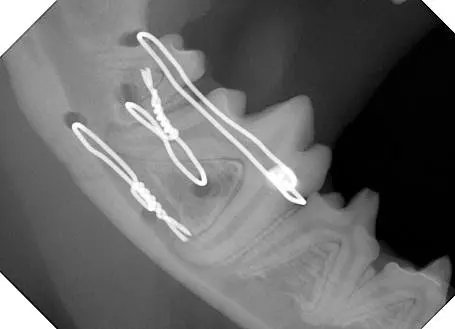

Figure 2. Radiograph of the same dog’s mandible after fixation with transosseous wires.

Numerous techniques may be used to stabilize a jaw fracture. The technique is usually determined once the fracture has been characterized. Oversized muzzles are used to either hold the patient in occlusion until the fracture is further stabilized or is used as the primary form of fracture stabilization. Interdental splints using wire and composite material around the crowns of the teeth, encircling cerclage wires around the mandibles, and intraosseous wires across a fracture are all techniques used to stabilize a jaw fracture.